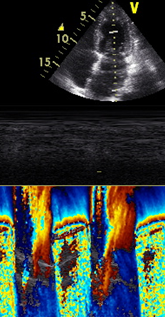

Sezioni Parasternali

Sezioni Apicali

Sezioni Sottocostali

Sezioni Sovrasternali